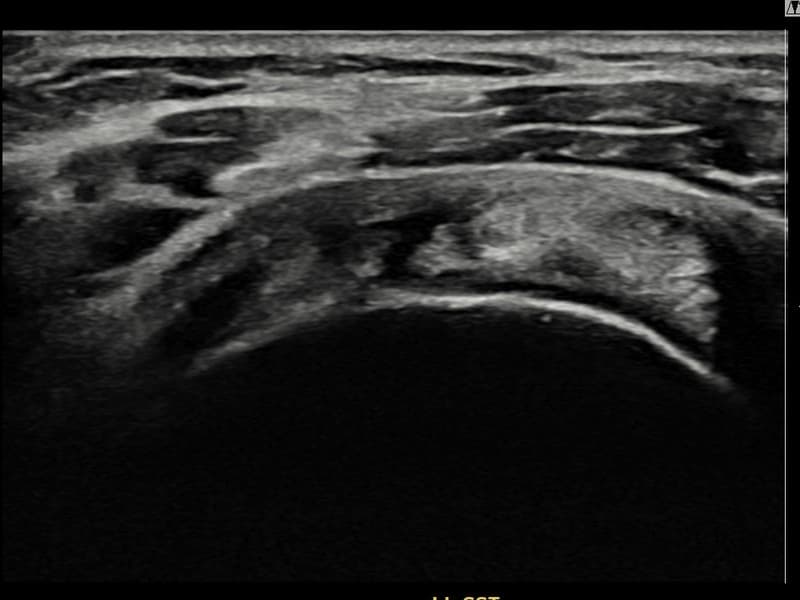

Before

시술 전 초음파 측정 결과 파열 크기는 14mm × 7mm (힘줄 두께의 약 65% 결손)로 확인되었습니다. 시술 전 초음파에서 좌측 극상근건 점액낭면측의 광범위한 에코 소실과 힘줄 경계의 불규칙성이 확인되었습니다. 시술 후 초음파에서 힘줄 경계가 정상화되고 에코 패턴이 균질하게 회복된 것이 관찰되었습니다.

50대 초반 여성 환자분으로, 가사 노동과 직장 업무를 병행하며 왼쪽 어깨 통증이 점점 심해져 내원하셨습니다. 초음파 검사에서 좌측 극상근건 점액낭면측의 광범위 부분파열이 확인되었으며, 파열 면적이 넓어 일반적인 보존적 치료로는 구조적 회복이 어렵다고 판단하였습니다. 초음파 유도 하 축소봉합술을 시행하였고 시술 당일 귀가하셨으며, 이후 체계적인 재활 프로그램을 진행하였습니다. 시술 13주 후 추적 초음파에서 힘줄 연속성이 안정적으로 회복되고 점액낭면측 경계가 정상화된 것이 확인되어 통증 없이 직장 복귀에 성공하셨습니다.